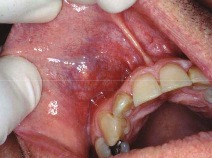

mucocele

Front

-localized tissue swelling that increases and decreases in size most commonly on lower lip -severed salivary gland duct -mucous filled